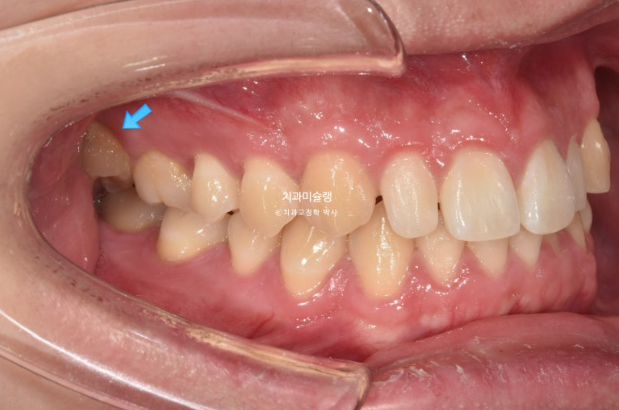

이 환자분이 한쪽으로만 씹었던 이유는 반대쪽에 가위교합이 있었기 때문입니다.

파란 화살표가 가위교합이고 위 큰어금니는 바깥으로 나가있고 대합치는 안쪽으로 쓰러지며 가위처럼 서로 엇갈려 교합되는 상태를 말합니다.

파란 화살표 치아가 바깥으로 뻗치면서 가위교합의 원인이 됩니다.